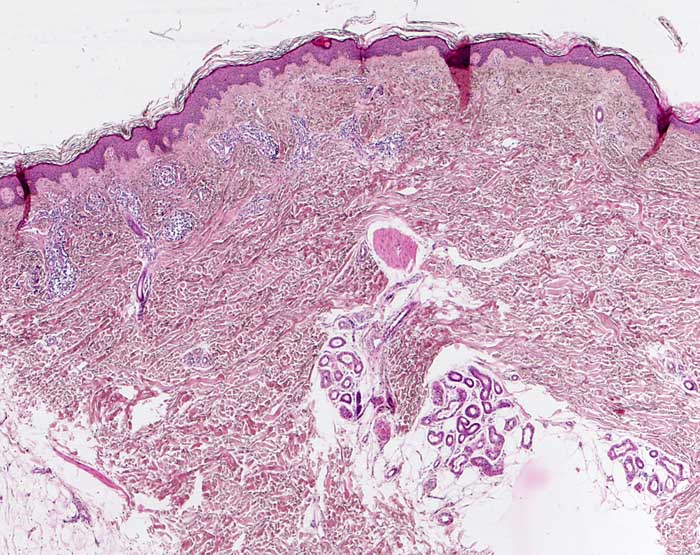

normale Felderhaut vom Oberschenkel

Das Korium der Oberschenkelhaut ist etwas dünner als das Korium der Rückenhaut. Haare sind nicht sehr zahlreich und reichen nicht sehr tief. In diesem Anschnitt ist lediglich ein Musculus arrector pili sichtbar, der auf die Anwesenheit eines Haarfollikels hindeutet.

25